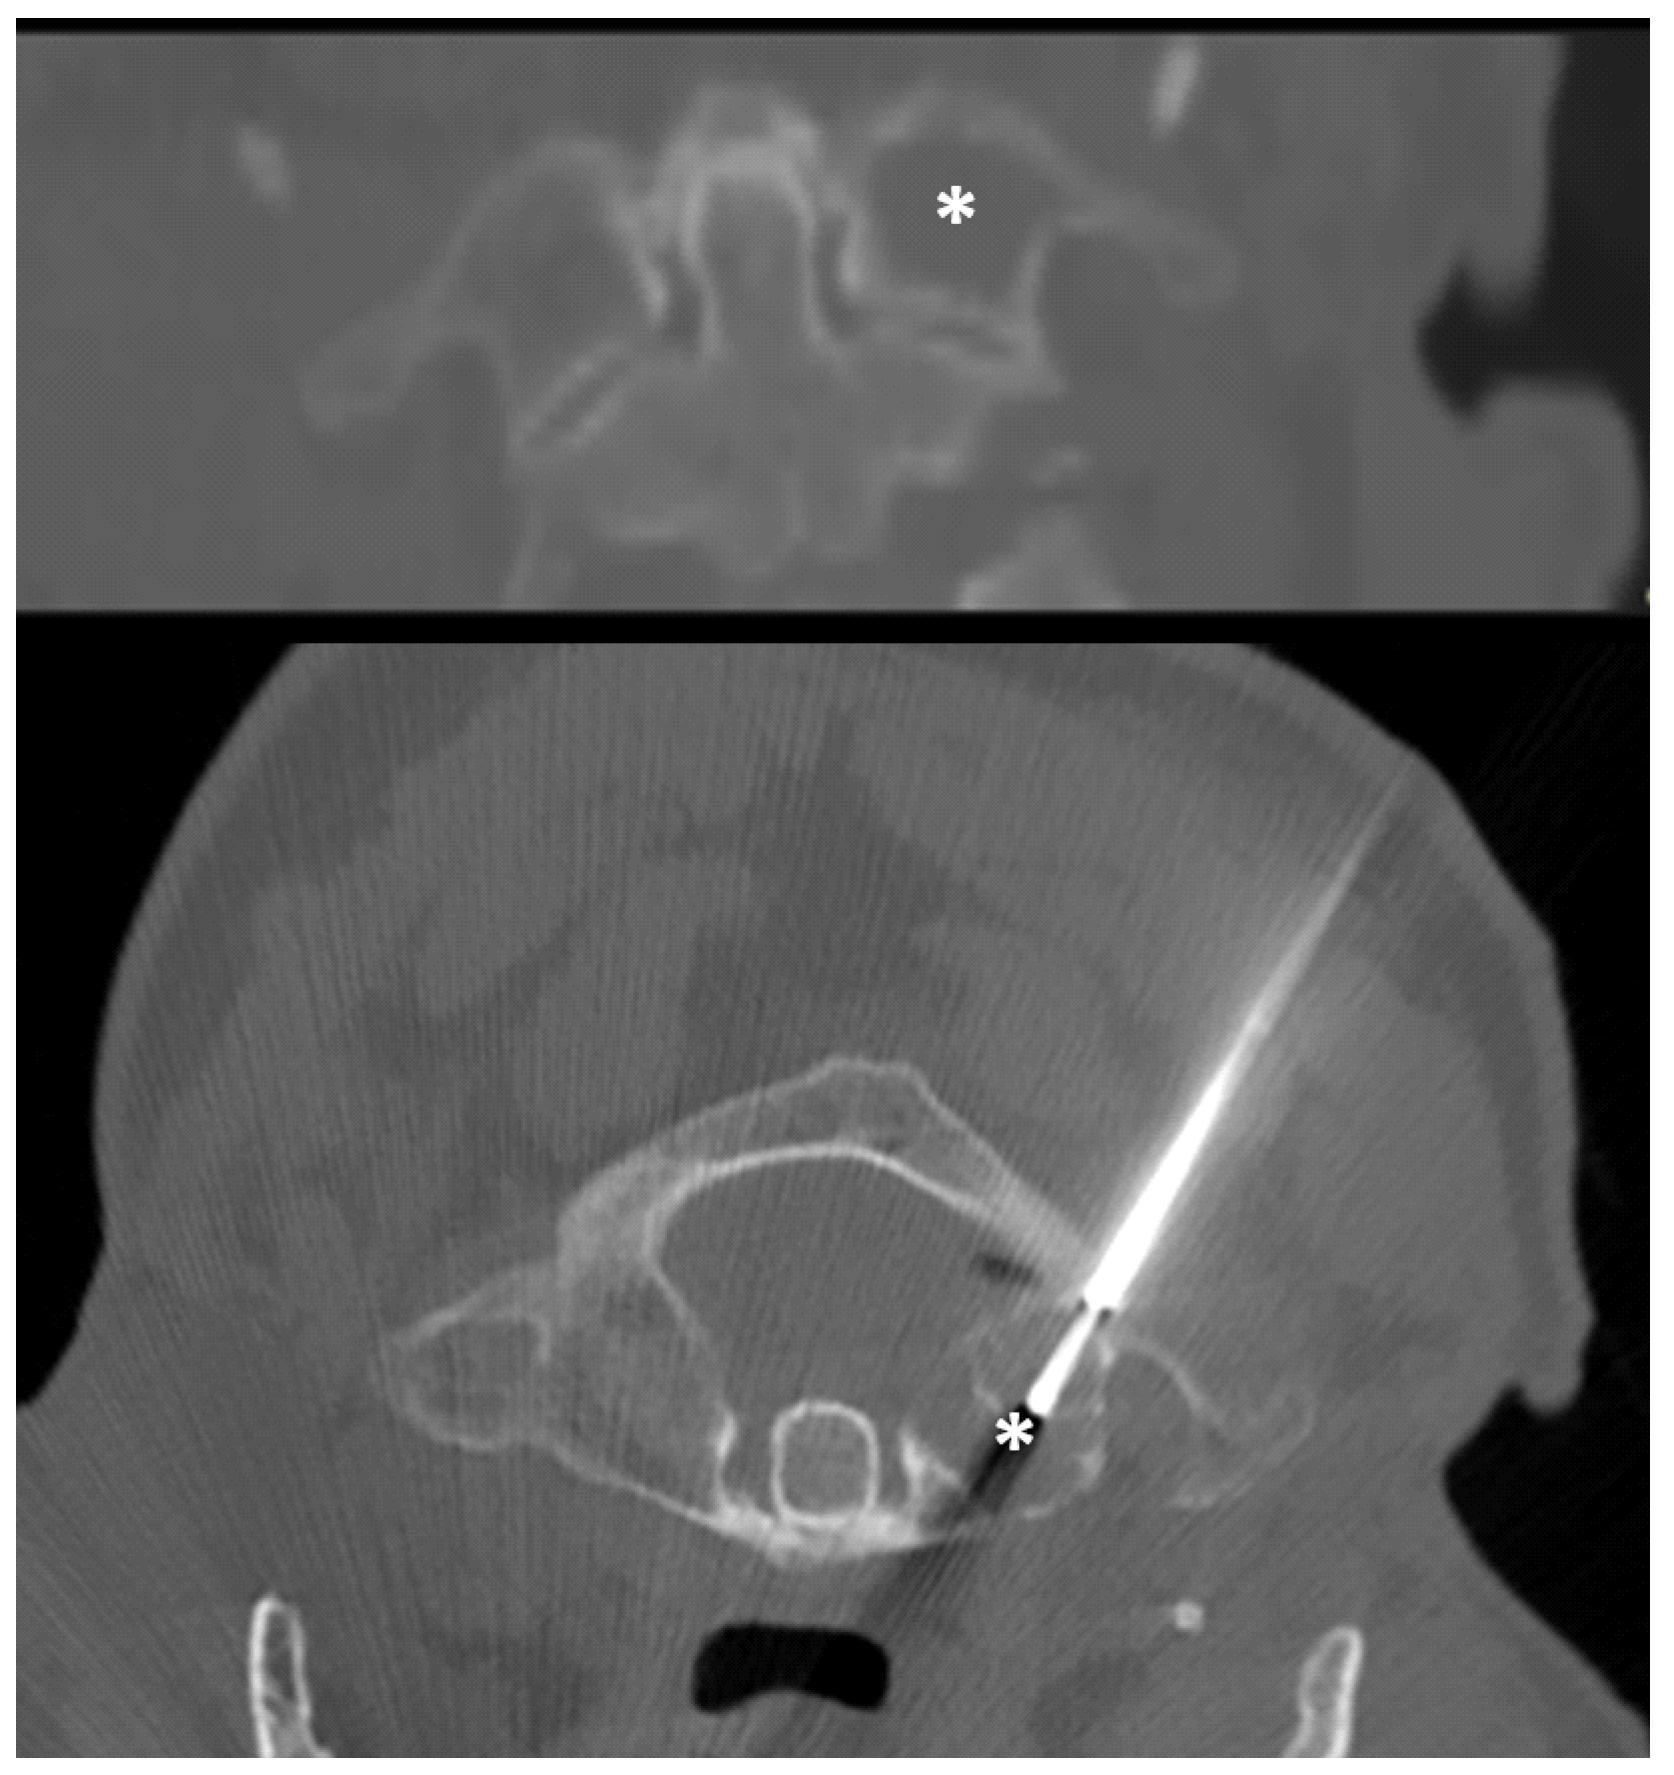

| 1 | 18, M | C2 | Osteolytic | 14 | No | Posterior | Aneurismal bone cyst |

| 2 | 71, M | C2 | Osteolytic | 14 | No | Posterior | Multiple myeloma |

| 3 | 49, M | C1 | Osteolytic | 14 | No | Posterior | Aggressive hemangioma |

| 4 | 64, F | C2 | Osteolytic | 14 | Yes | Lateral | Multiple myeloma |

| 5 | 64, F | C1 | Osteolytic | 14 | No | Posterior | Metastasis (breast cancer) |

| 6 | 40, F | C2 | Osteolytic | 14 | No | Posterior | Metastasis (breast cancer) |

| 7 | 39, M | C1 | Osteolytic | 14 | No | Posterior | Multiple myeloma |

| 8 | 16, M | C2 | Osteolytic | 14 | No | Posterior | Aneurismal bone cyst |

| 9 | 79, M | C2 | Osteolytic | 14 | Yes | Lateral | Non-diagnostic |

| 10 | 23, M | C1 | Osteolytic | 14 | No | Posterior | Blood and fibrin (non-diagnostic) |

| 11 | 73, M | C1 | Mixed | 14 | No | Posterior | Metastasis (prostate cancer) |

| 12 | 52, F | C0 and C1 | Osteolytic | 14 | Yes | Posterior | Multiple myeloma |

| 13 | 28, F | C1 | Osteolytic | 14 | No | Posterior | Aneurismal bone cyst |

| 14 | 72, F | C1 and C2 | Sclerotic | 12 | No | Posterior | Pseudogout |

| 15 | 51, F | C1 and C2 | Osteolytic | 14 | Yes | Posterior | Rare giant cells (non-diagnostic) |

| 16 | 86, F | C0 | Osteolytic | 12 | No | Posterior | Metastasis (breast cancer) |